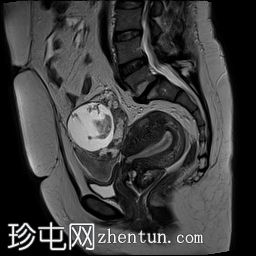

矢状位

T1加权像(脂肪抑制)

可见子宫外腹腔内妊娠囊,内含胎儿组织。

该妊娠囊向后推移子宫,并与剖宫产瘢痕凹陷处紧密相连。

该妊娠囊与相关肠袢无法分离。可见其与性腺血管密不可分,且性腺血管明显突出。

胎盘位于妊娠囊后方,紧贴子宫前壁。

沿妊娠囊下缘可见一处异质性局灶性积液,最大轴向尺寸约为 8.4 × 5.5 cm,T1 加权像呈异质性高信号,T2 加权像呈异质性中等信号,T1 脂肪抑制序列未见信号下降,提示为血液成分。该积液压迫膀胱。

可见周围脂肪间隙呈条索状改变。

子宫体积增大,后倾,子宫内膜厚度约 1 cm,子宫下段前壁可见局灶性变薄(既往子宫瘢痕)。子宫连接区完整,未见肌层肿块。可见子宫内膜腔边缘有血性分泌物。